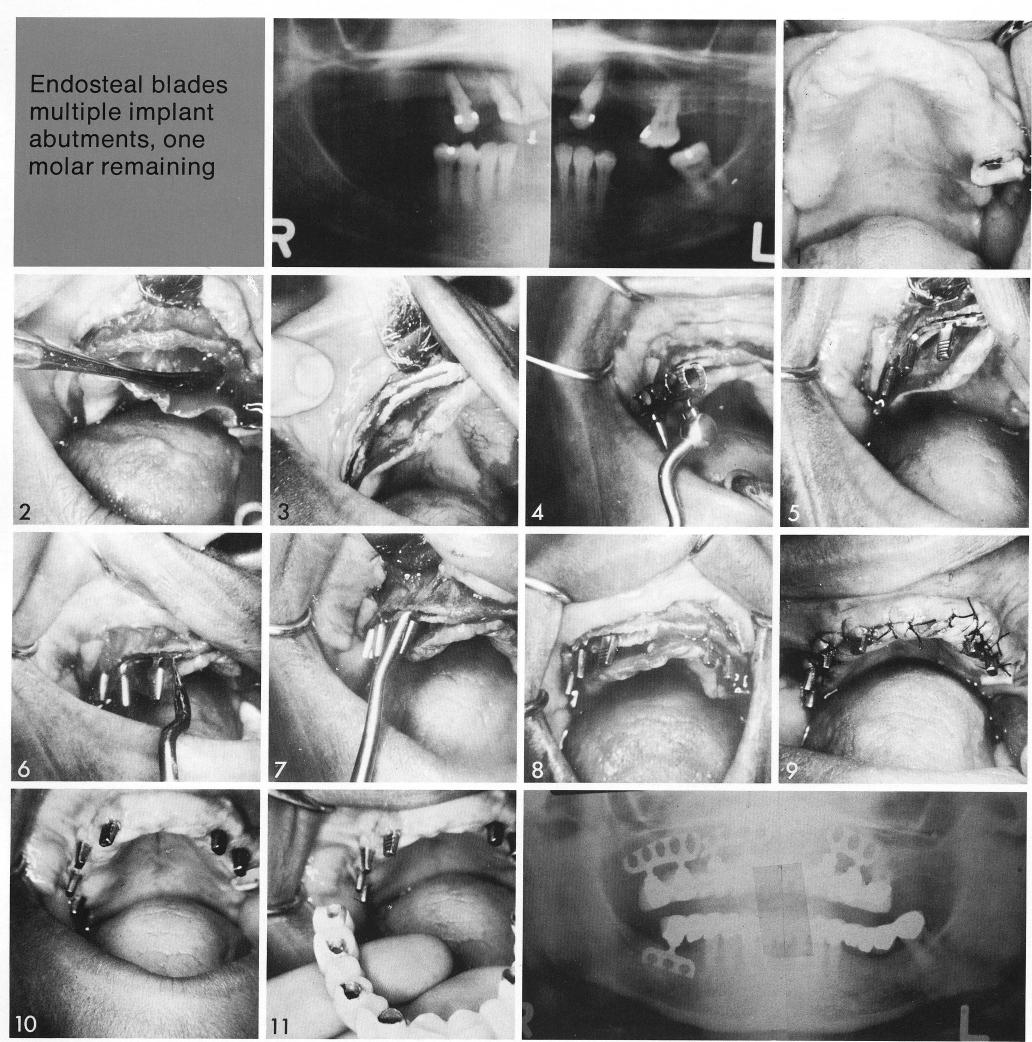

Endosteal blades

multiple implant abutments, one molar remaining

A beautiful example of the deceptive padding of maxillary soft tissues! An apparently thick ridge (1) was severely undercut (2). The ridge was not reduced, leaving the extra bone at the crest, but the bladevent sockets were angled decidedly palatally (3) to avoid the undercut. Bladevents were inserted. Because of the bone picture and the socket angle, it was necessary to withdraw the bladevent with a modified crown and bridge remover (7) to countersink the posts (8). A f ter healing (10), impressions were taken for the final prosthesis (11).

1 Thick maxillary ridge with severe undercut for implantation